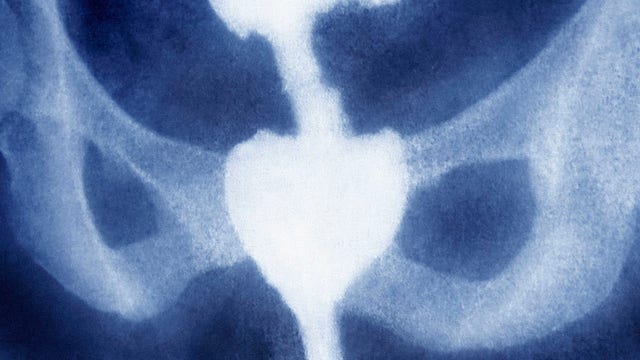

Drinking milk can increase risk of developing prostate cancer, study finds

Prostate cancer is the second leading cause of cancer death in American men, according to the American Cancer Society.